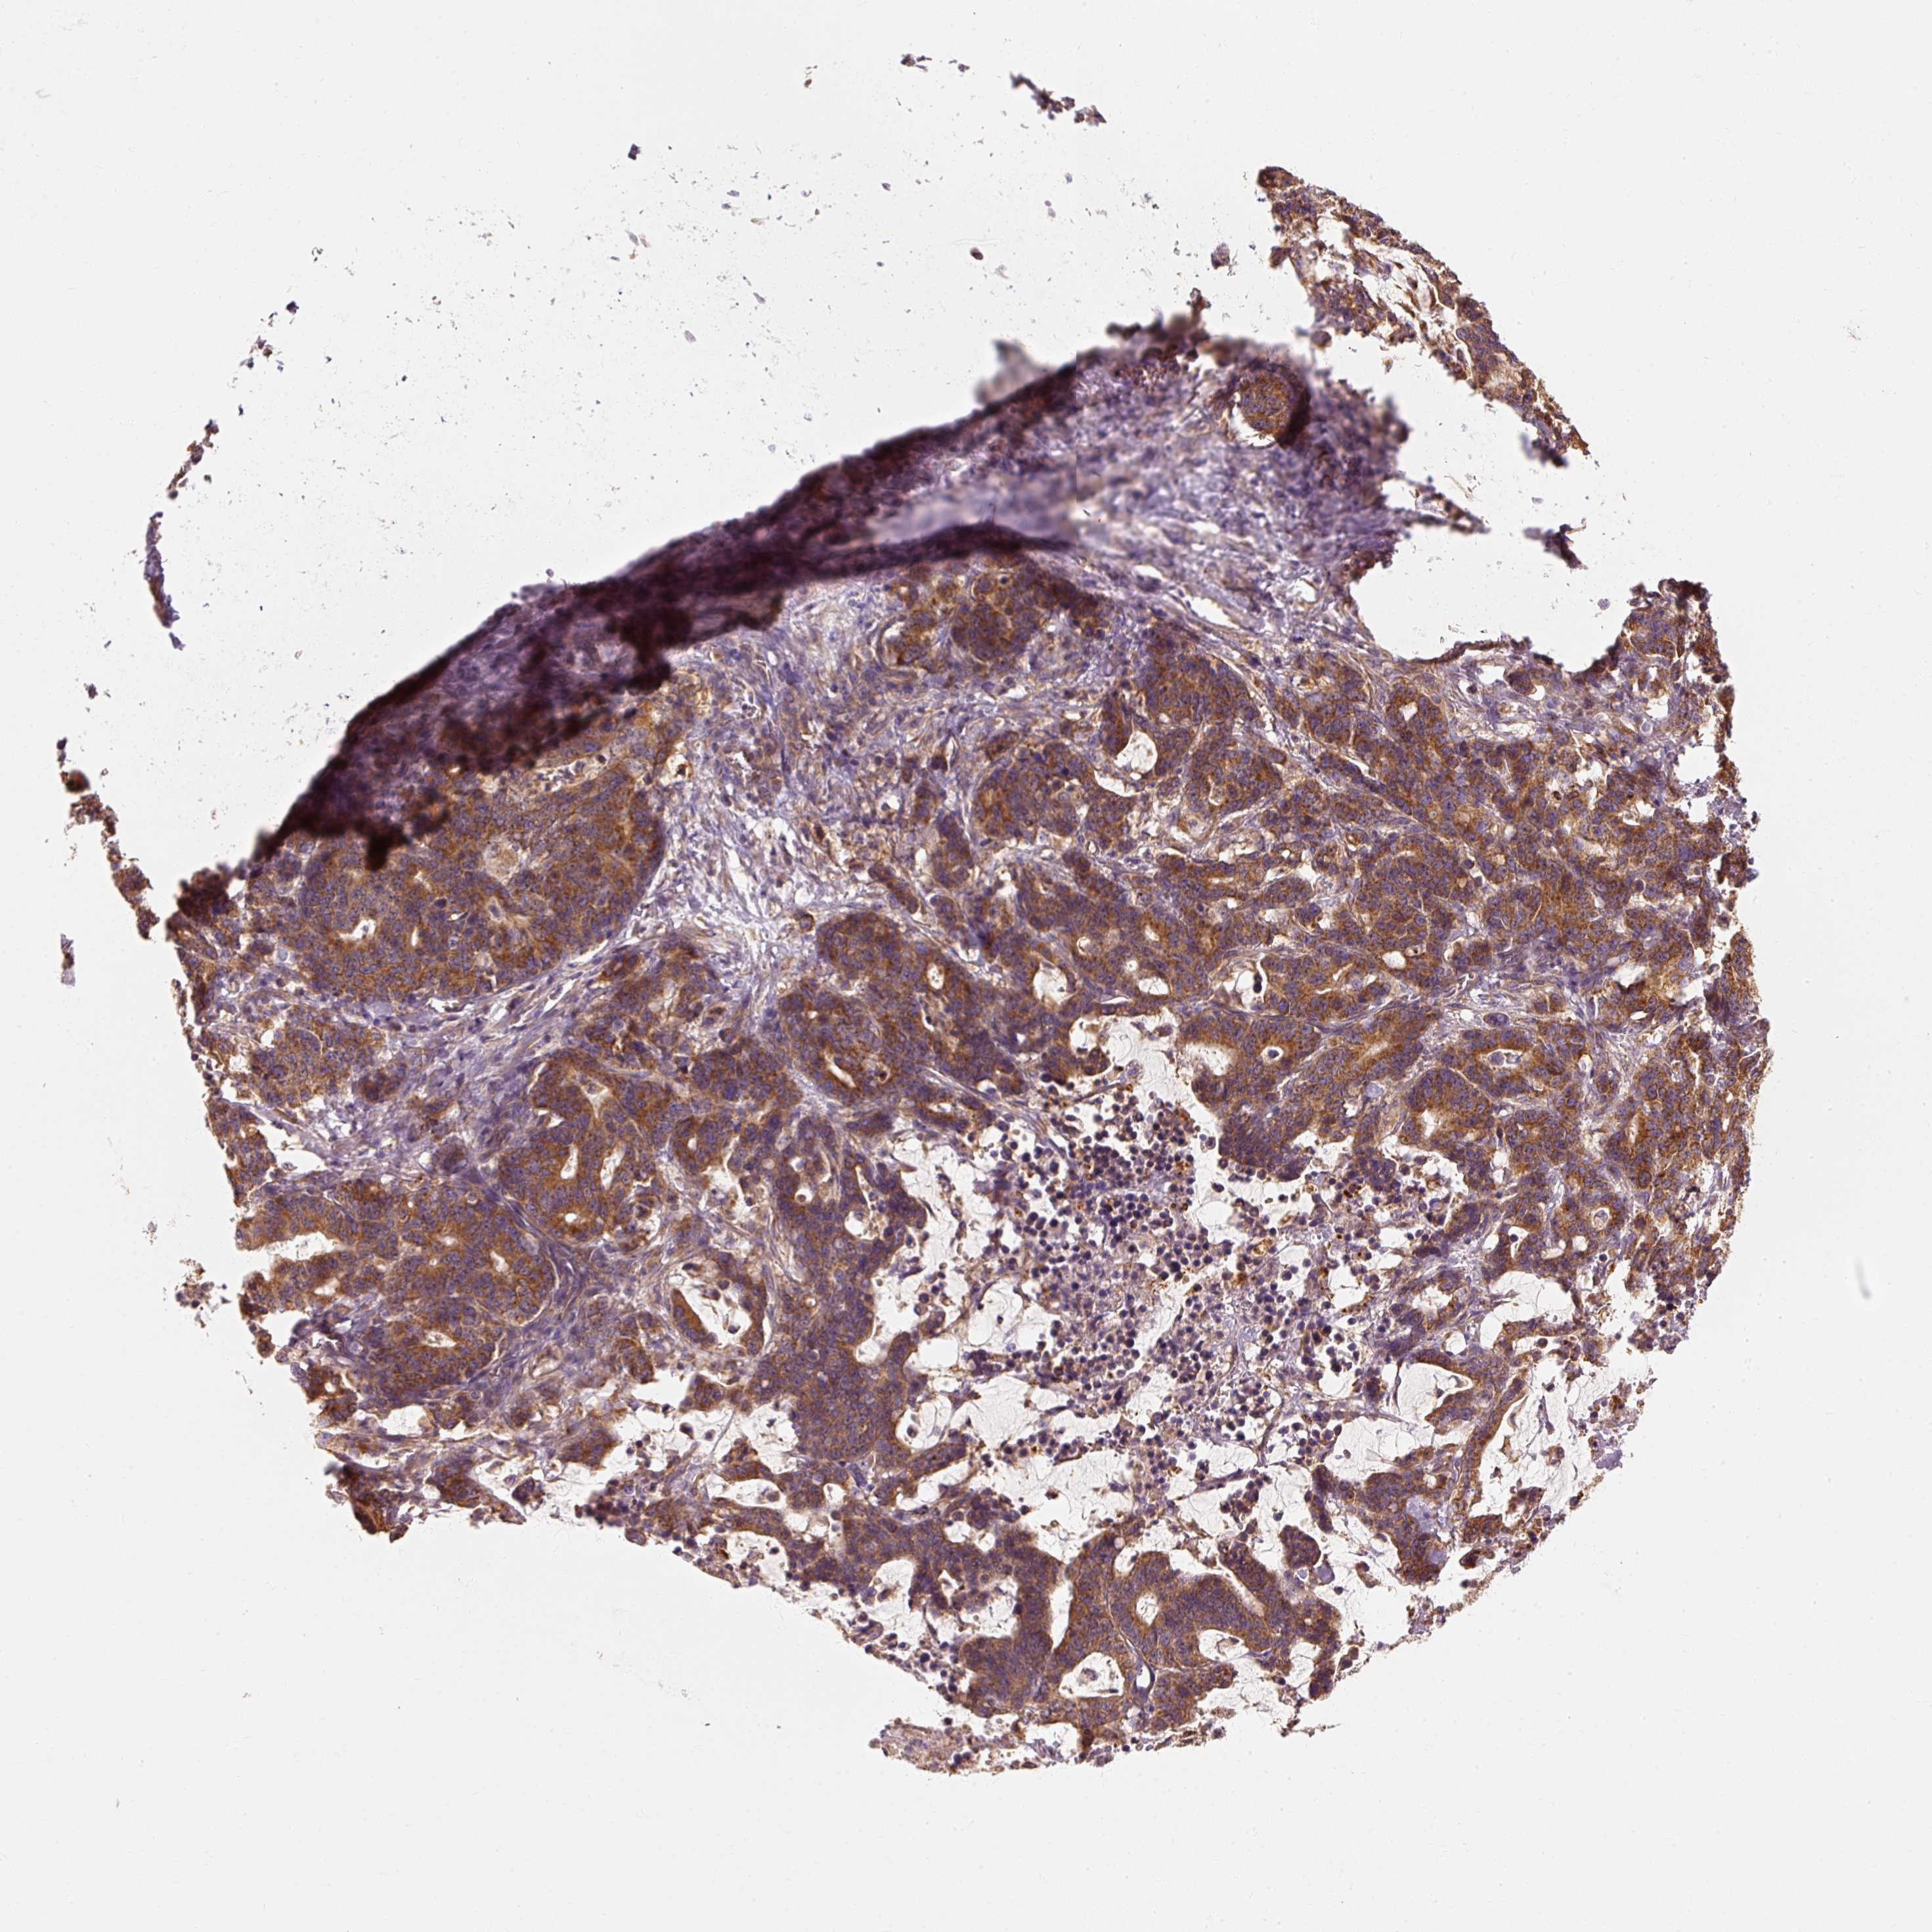

STOMACH CANCER - Protein expressioni

A mouse-over function shows sample information and annotation data. Click on an image to view it in a full screen mode. Samples can be filtered based on level of antibody staining by selecting one or several of the following categories: high, medium, low and not detected. The assay and annotation is described here.

Note that samples used for immunohistochemistry by the Human Protein Atlas do not correspond to samples in the TCGA dataset.

Antibody stainingi

Antibody staining in the annotated cell types in the current human tissue is reported as not detected, low, medium, or high, based on conventional immunohistochemistry profiling in selected tissues. This score is based on the combination of the staining intensity and fraction of stained cells.

Each image is clickable and will lead to virtual microscopy that enables deeper exploration of all samples and also displays staining intensity scores, fraction scores and subcellular localization as well as patient and tissue information for each sample.

Antibody HPA036231

Antibody HPA036232

Staining

High

Medium

Low

Not detected

Intensity

Strong

Moderate

Weak

Negative

Quantity

>75%

75%-25%

<25%

None

Location

Nuclear

Cytoplasmic/membranous

Cytoplasmic/membranous,nuclear

Adenocarcinoma, NOS